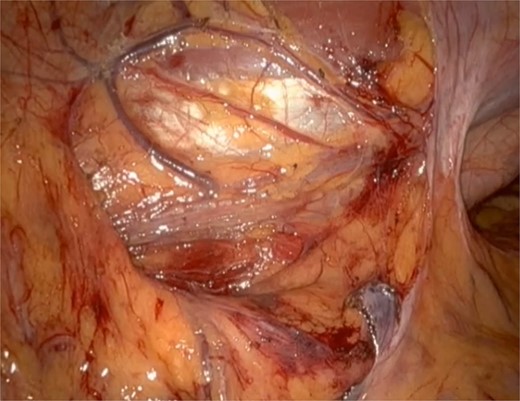

He underwent a robotic excision of his paraganglioma in a right lateral position, using a transperitoneal approach with three robotic ports and one assistant port in the midline. The left colon was mobilized medially, exposing the tumour. After identifying the ureter and gonads, the tumour was dissected freely using a vessel sealer, before removing it in a specimen bag. Operation was uneventful (Figs 3 and 4).

Well circumscribed mass with extensive vascularisation is located and isolated, with no surrounding tissue necrosis or invasion observed. Real time video footage revealed a pulsatile mass.